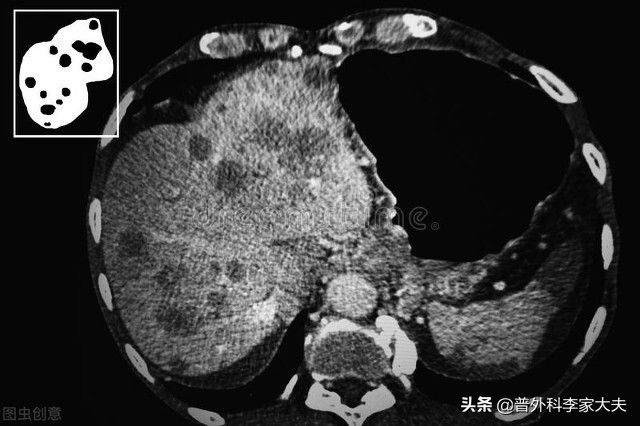

肝癌起病隐匿,早期缺乏典型症状,加上我国未广泛开展肝癌的普查工作,因此,肝癌患者的发现多数是因出现临床就医才发现的。但有典型临床症状才发现的肝癌患者,多数疾病已经进入了肝癌晚期。但不管如何,延长生命与提高生活质量,仍然是所有肝癌晚期患者的追求,饮食是既是人体正常生理需求的必需,也是保证肝癌营养来源与抗癌治疗的基础,但不健康的饮食,对肝癌晚期患者来说,也是不利于疾病恢复,甚至会危及患者生命。如何饮食才有利于肝癌晚期的健康呢?总结起来,肝癌晚期患者应该注意以下几方面情况:

肝癌